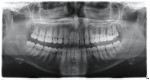

A 19-year-old female patient presented with the chief complaint of not being happy with her smile (Figure 1 through Figure 4). After a comprehensive examination, the patient was found to have a congenitally missing tooth No. 9, macrodontia of tooth No. 8, and a Class II molar relationship on the right side with minor spacing and rotations throughout the arch.

A 41-year-old male patient presented with the chief complaint of “excessive space between his teeth.” After a comprehensive examination, the patient was found to have congenitally missing maxillary lateral incisors and generalized gingival recession (Figure 22 through Figure 27). Additional orthodontic problems identified included an anterior open bite, upper and lower arch size discrepancies, spacing issues, a right side posterior cross bite, and a left side “scissor bite.”